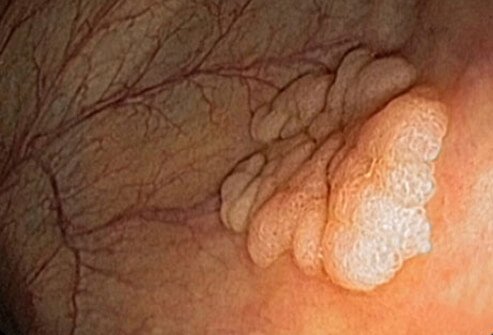

Get Checked for Cervical Cancer

Pap Smears Are Critical for Detection

With regular Pap smears, cervical cancer (pictured) is easy to prevent. The cervix is a narrow passageway between the uterus (where a baby grows) and the vagina (the birth canal). Pap smears find abnormal cells on the cervix, which can be removed before they ever turn into cancer. The main cause of cervical cancer is the human papillomavirus (HPV), a type of STD.

Screening for STIs

What Is a Pap Test?

During a Pap smear, the physician takes a scraping of cells from the cervix. The cells are analyzed in a lab. The sample can be checked for HPV, the virus that causes cervical malignancies. Other kinds of testing hat can be performed at the time of pelvic examination include tests that can also detect gonorrhea and chlamydia. A woman should be tested for those annually if she is sexually active. Certain STIs increase the potential for health problems in unborn babies, so expectant mothers should be tested for these infections and treated if they test positive for them.